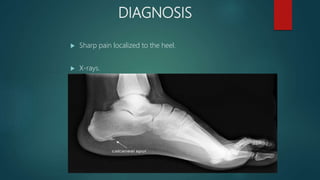

DIAGNOSIS

 Sharp pain localized to the heel.

 X-rays.